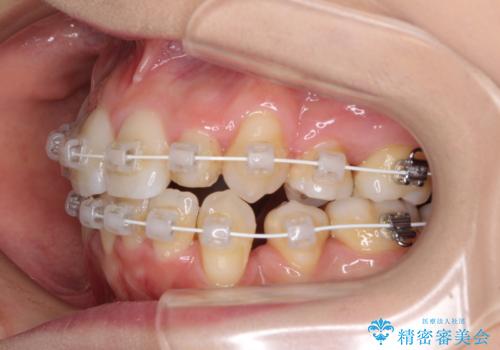

- 矯正装置

- 審美装置

- 結婚式に向けて、八重歯と虫歯で変色した歯を改善したいとのことで来院された患者様です。

上下ともにデコボコが強いため、上下顎左右小臼歯各1歯を抜歯して歯列を整えることとしました。

大きな虫歯が認められた歯は、矯正治療後にオールセラミッククラウンにて補綴治療を行うこととしました。

抜歯矯正は、2年半程度の治療期間を要することが一般的ですが、今回はセラミッククラウンによる補綴治療も含めて2年1ヶ月で終えることができました。